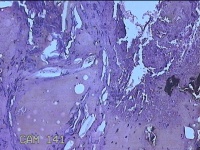

性别

女

年龄

28岁

临床诊断

1.疖肿病 2.皮脂腺囊肿

一般病史

外阴部起丘疹疼痛一周。

标本名称

外阴部包块

大体所见

灰白暗红色包块1x0.7x0.3cm一个,表面糜烂。